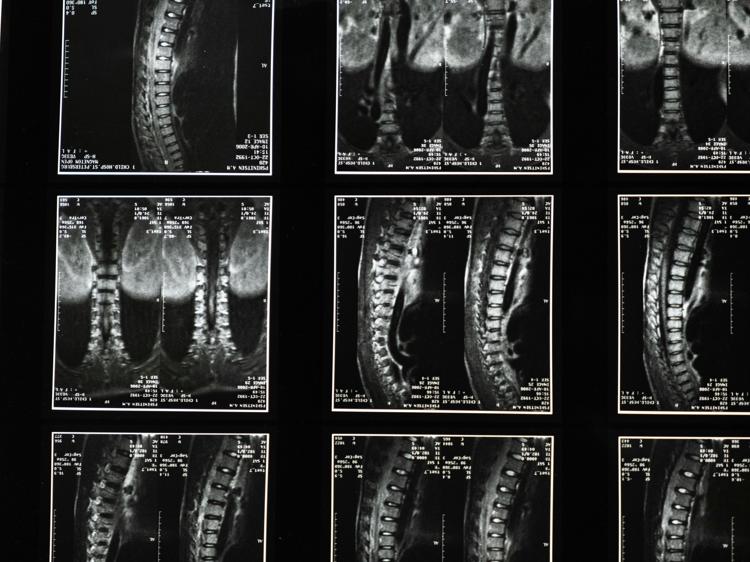

脊髓炎是一种累及脊髓的神经系统疾病,西医一般会针对病因采取规范治疗,而中医则从整体观出发,通过调节身体机能、改善内环境来辅助促进恢复,两者结合能更好地帮患者应对疾病。不少人对中医调理脊髓炎的具体方法有疑问——比如中药是不是随便吃补药就行?针灸有没有副作用?今天就从核心逻辑到实际操作,详细拆解中医辅助调理脊髓炎的关键内容。

中医认为,脊髓炎的发生与“正气不足”和“外邪入侵”密切相关——正气就像身体的“防御部队”,当正气虚弱时,风、寒、湿等外邪容易趁机侵入经络,导致气血运行不畅、脊髓失养,进而出现肢体无力、感觉异常等症状。这种理念区别于西医针对局部炎症的治疗,更注重恢复身体的“平衡状态”:一方面通过“扶正”增强机体抵抗力,另一方面通过“祛邪”清除阻滞经络的病邪,让气血能顺畅滋养脊髓和神经组织。需要注意的是,中医调理是辅助手段,不能替代西医的病因治疗,比如急性脊髓炎的激素冲击疗法,若单独依赖中医可能会延误病情。